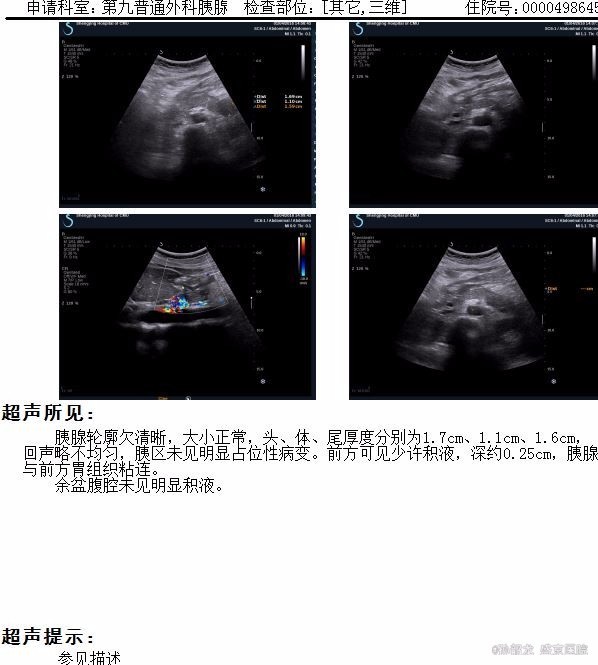

查体: 双侧乳腺缺如。腹平坦,未见胃肠型及蠕动波,腹壁无静脉曲张,左腹部可见经腹直肌切口瘢痕约20cm,以及两点状瘢痕。肝脾肋下未触及,未触及包块,全腹轻压痛,反跳痛,腹直肌紧张。Murphy’s征阴性,肝肾区无叩痛,移动性浊音阴性,肠鸣音4次/分。 辅查: 胰腺CT提示胰腺稍肿胀,轮廓模糊,胰周见模糊渗出及积液,胰腺前方腹腔内渗出。左侧肾前筋膜及邻近腹膜增厚,左侧结肠旁沟内见积液。 肝脏密度仍减低;胆囊内胆汁密度增高。扫描范围左侧胸腔积液。 腹部BUS 提示腹腔积液。 血淀粉酶和脂肪酶明显升高,血甘油三酯和胆固醇升高。

诊断: 高脂血症性胰腺炎 治疗:入院后胃肠减压,禁食水,中心静脉穿刺补液,抑制胰酶,降血脂治疗,由于腹腔有积液,彩超引导下穿刺,引出略带暗红色积液,化验积液淀粉酶,并不高,说明胰腺炎并不严重。至治疗1周左右,停用抑酶药物,复查血脂,TG降至2.62 mmol/L,引流液逐渐减少,治疗10日复查腹部彩超,几乎无积液,拔除引流管,病人腹胀痛症状明显好转,拔除胃管,清淡饮食,治疗12日顺利出院。嘱继续口服降脂药物,低脂饮食。